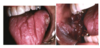

What is this radiographic & clinical findings?

Periapical cyst

shows inflammation at site

abscess developed fistula tract thru

soft tissue. Pt will have pain until

pressure is released